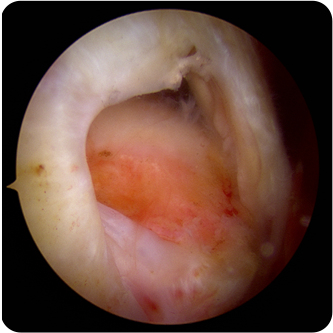

회전근개파열의 여러 모습들

회전근개가 완전히 파열되었고 오랜시간이 경과한 경우에는 끊어진 힘줄이 말려 들어가서 봉합이 불가능하거나

어깨 전체의 근육 위축을 유발할수있습니다.